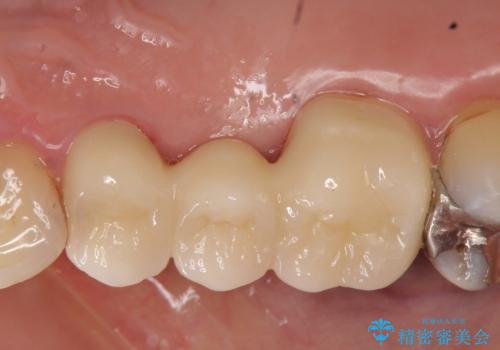

オールセラミッククラウン 歯根破折→抜歯→ブリッジ

- オールセラミッククラウン…¥100,000×3、仮歯…¥10,000×3費用は治療当時の料金となります

今回用いたオールセラミッククラウンはジルコニアフレームという白い素材の上にセラミックを盛っているため、審美性が非常に高いのが特徴です。

また、ジルコニアは人工ダイヤモンドの材料にも使われているほど高い強度を持っており、そのためオールセラミッククラウンは審美性だけでなく、奥歯やブリッジの補綴も可能とするクラウンです。